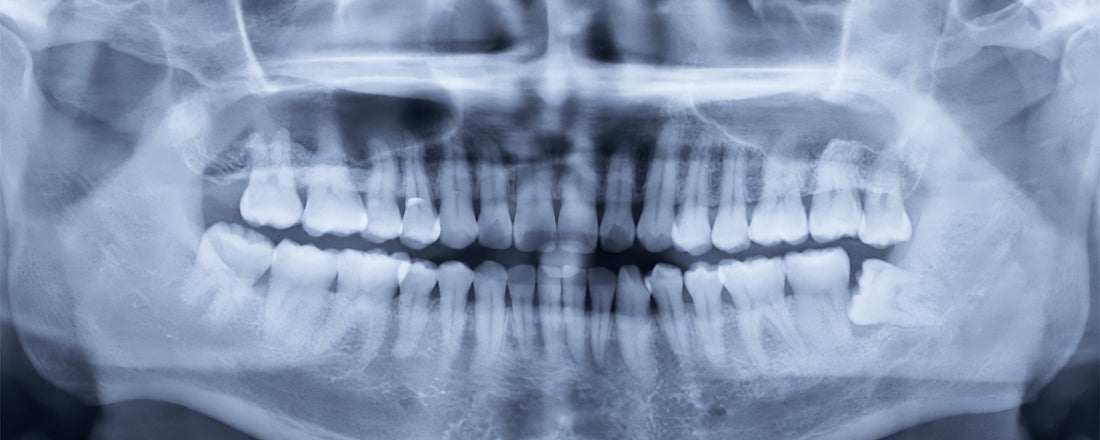

Obrázok 12: Horná čelusť. Všimnite si vertikálny šev (pripomínajúci "prasklinu") naprieč hornou čelusťou. Je to spojenie medzi časťami kosti, ktoré umožňuje určitú flexibilitu rastu čeluste. Podobné švy máme aj na lebke. Umožňujú jej rast počas dospievania.

Obrázok 17: American Journal of Orthodontics and Dento-facial Orthopedics: Mužská lebka predindustriálneho človeka zo 14. storočia (Oslo, Nórsko). Ľudia pred nástupom priemyselnej revolúcie nemali problémy s neprerezanými zubami múdrosti. Všimnite si, že nedochádza k tlačeniu zubov a maloklúzii.

Všetky nájdené lebky mali spoločné tri veci: mohutné dýchacie cesty, silné čeľuste a rovné zuby. Ľudia narodení pred viac ako 300 rokmi mali tieto rysy spoločné, pretože žuli nespracovanú stravu až 4 hodiny denne. 30,31